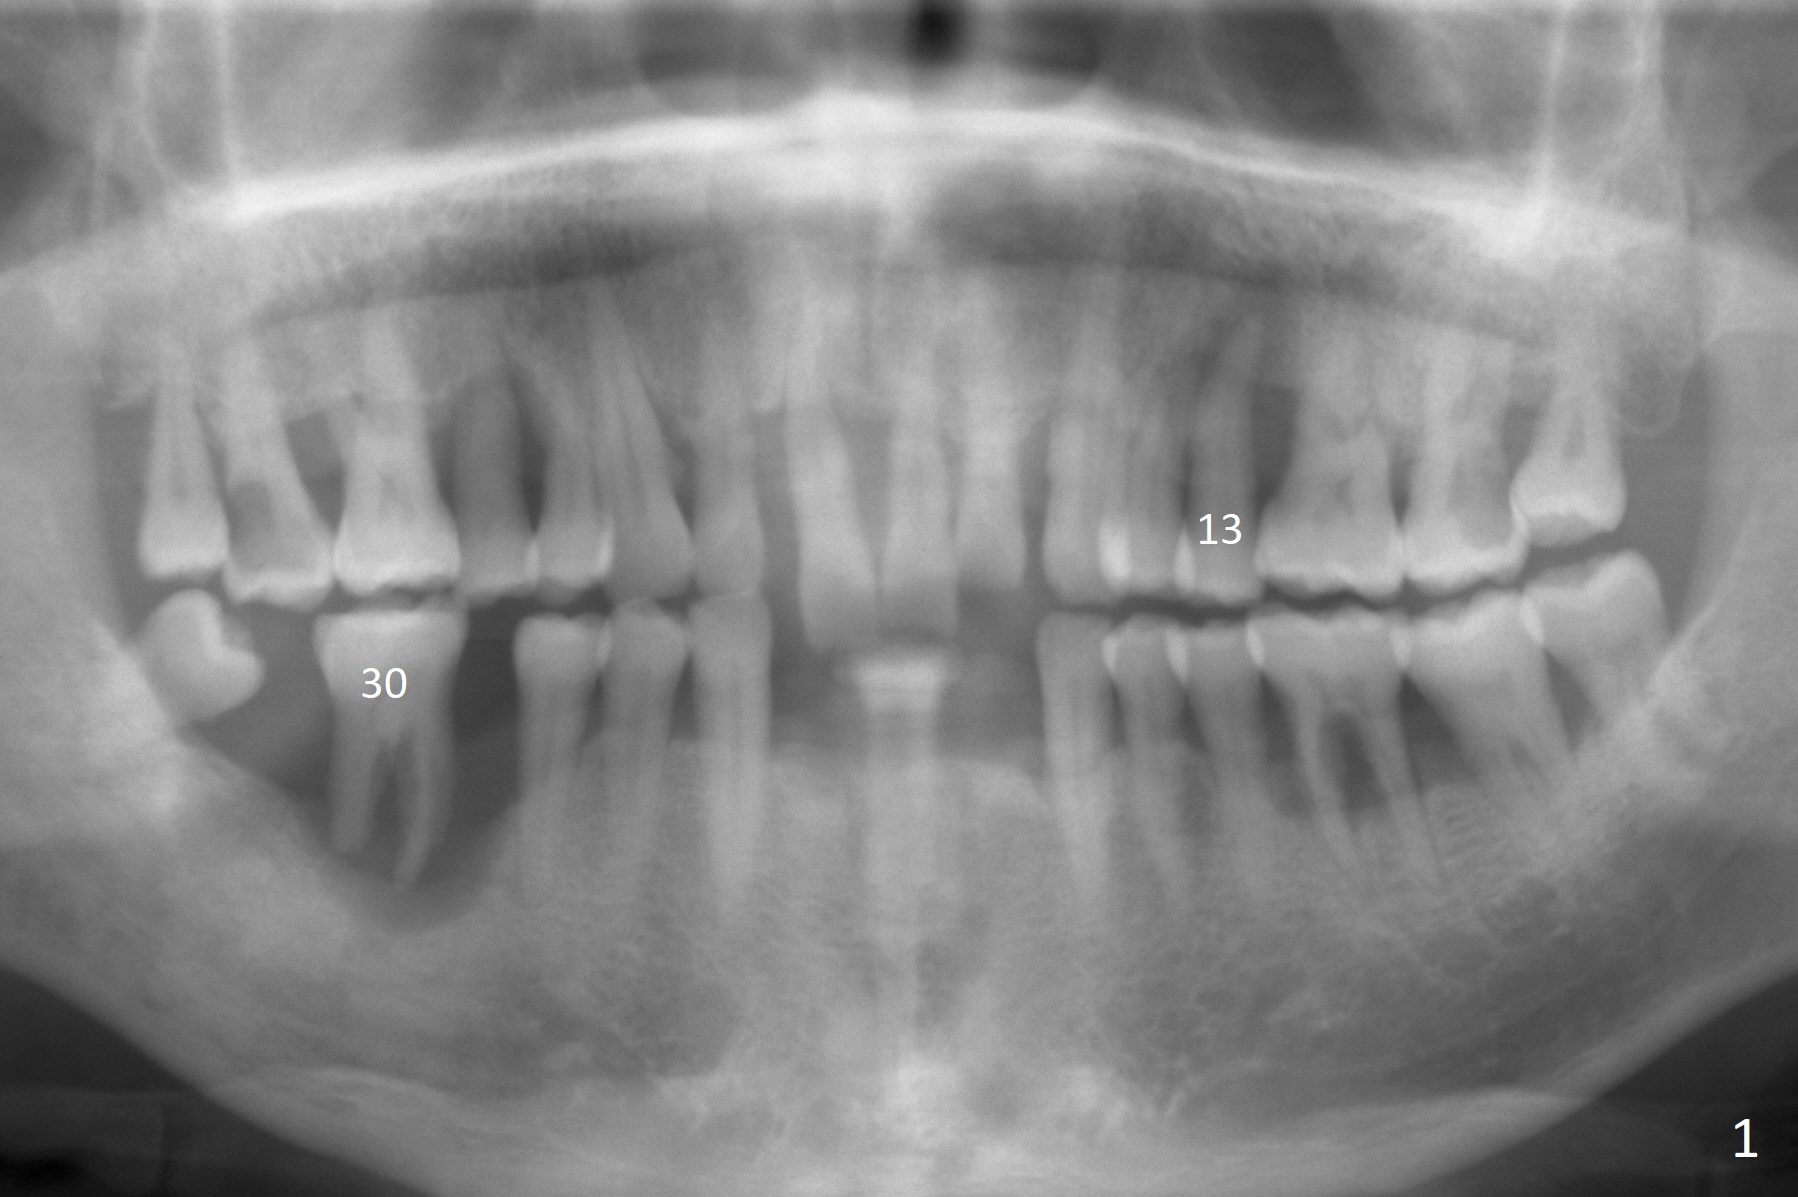

Drifting Molar A 57-year-old man has advanced periodontitis with bruxism. The mobile teeth #13 and 30 are his main concern (Fig.1). The tooth #30 has shifted distally. An implant will be placed in the mesial socket, if present. Due to severe bone loss, a 7 mm long abutment with 6 mm cuff is most likely to be used (Fig.2). Since the socket is huge, prepare large piece of gauze for hemostasis. Osteotomy should be initiated as buccal as possible, as the Inferior Alveolar Canal is near the lingual plate at the 1st molar. Prepare Sinus Master Kit. Why? Always take PA after initial drill to avoid violating the Canal. It may be ok to see the overlapping between the parallel pin and the Canal. Do not administer the Inferior Alveolar nerve block. Return to